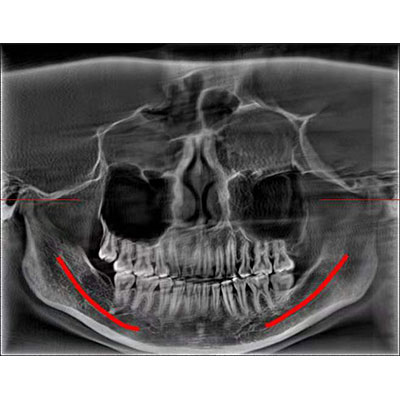

通過(guò)三維容積影像,提取高清口腔全景影像。

專有圖像校正技術(shù),去除金屬偽影,提高圖像分辨率。